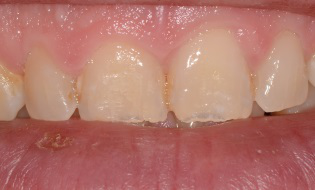

Cette jeune patiente présente une hypoplasie de son émail avec des colorations oranges et blanchâtres.

Le projet est de réaliser des facettes sur les 6 dents maxillaires antérieures, de canine à canine.

Résultat 1 mois après la pose des facettes. De très légères colorations ont été apportées pour respecter le sourire de la patiente.

Le sourire est naturel et agréable.